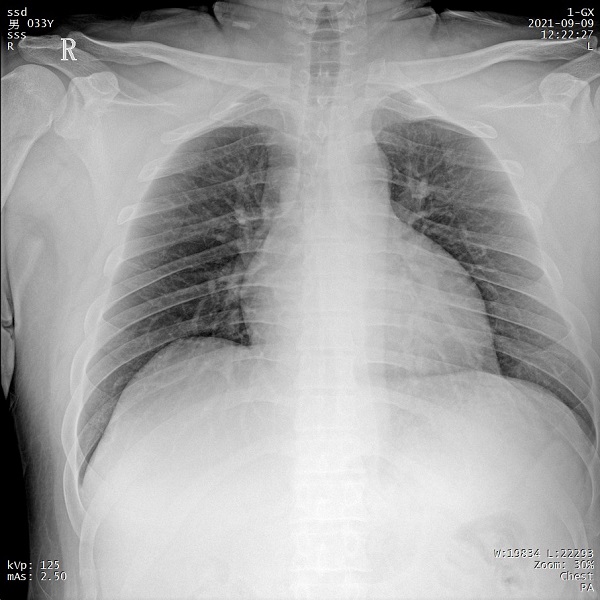

三、支持高千伏摄影 肺部纹理更有层次

PLX5500的最大可调千伏达到150kV,在达到一定高电压后,与骨骼相重叠的软组织或骨骼本身的细小结构及含气的管腔等,均可清晰显示。